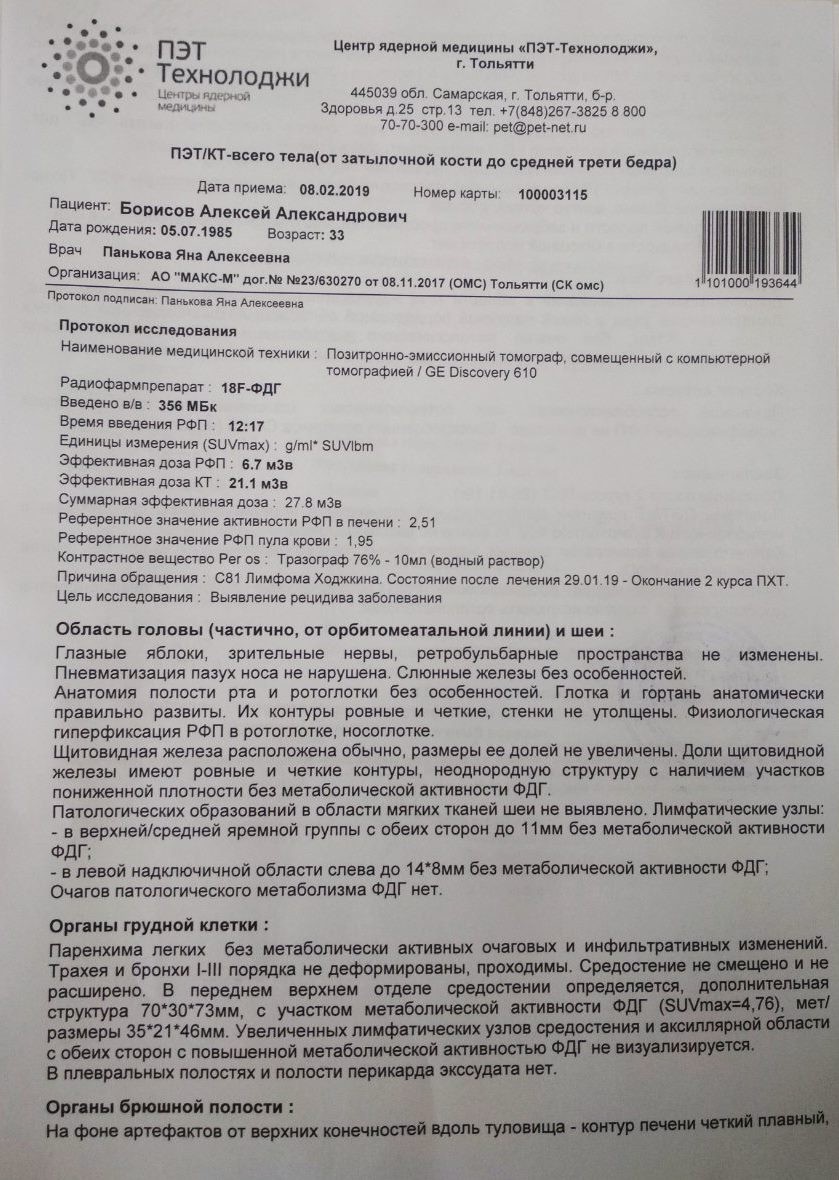

Диагностика лимфомы Ходжкина с помощью ПЭТ и КТ

Раздел: Светлые идеи